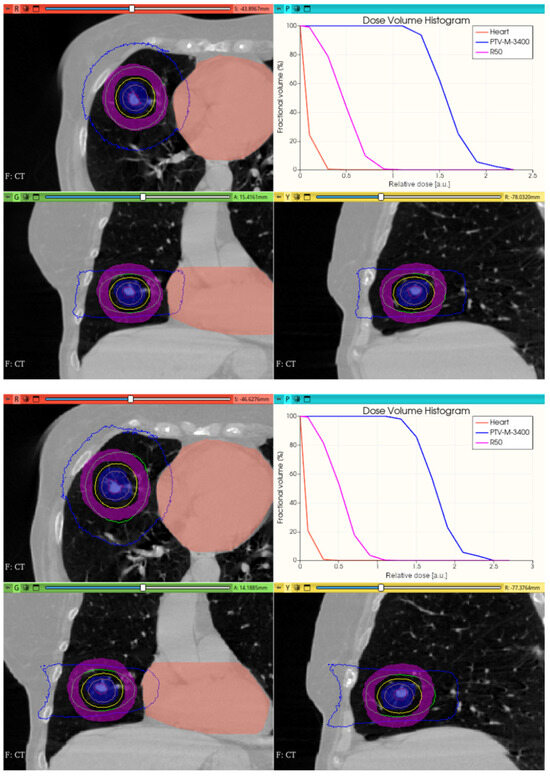

3.3.2. Preliminary CONVERAY Dosimetry Performance for Thoracic Irradiations